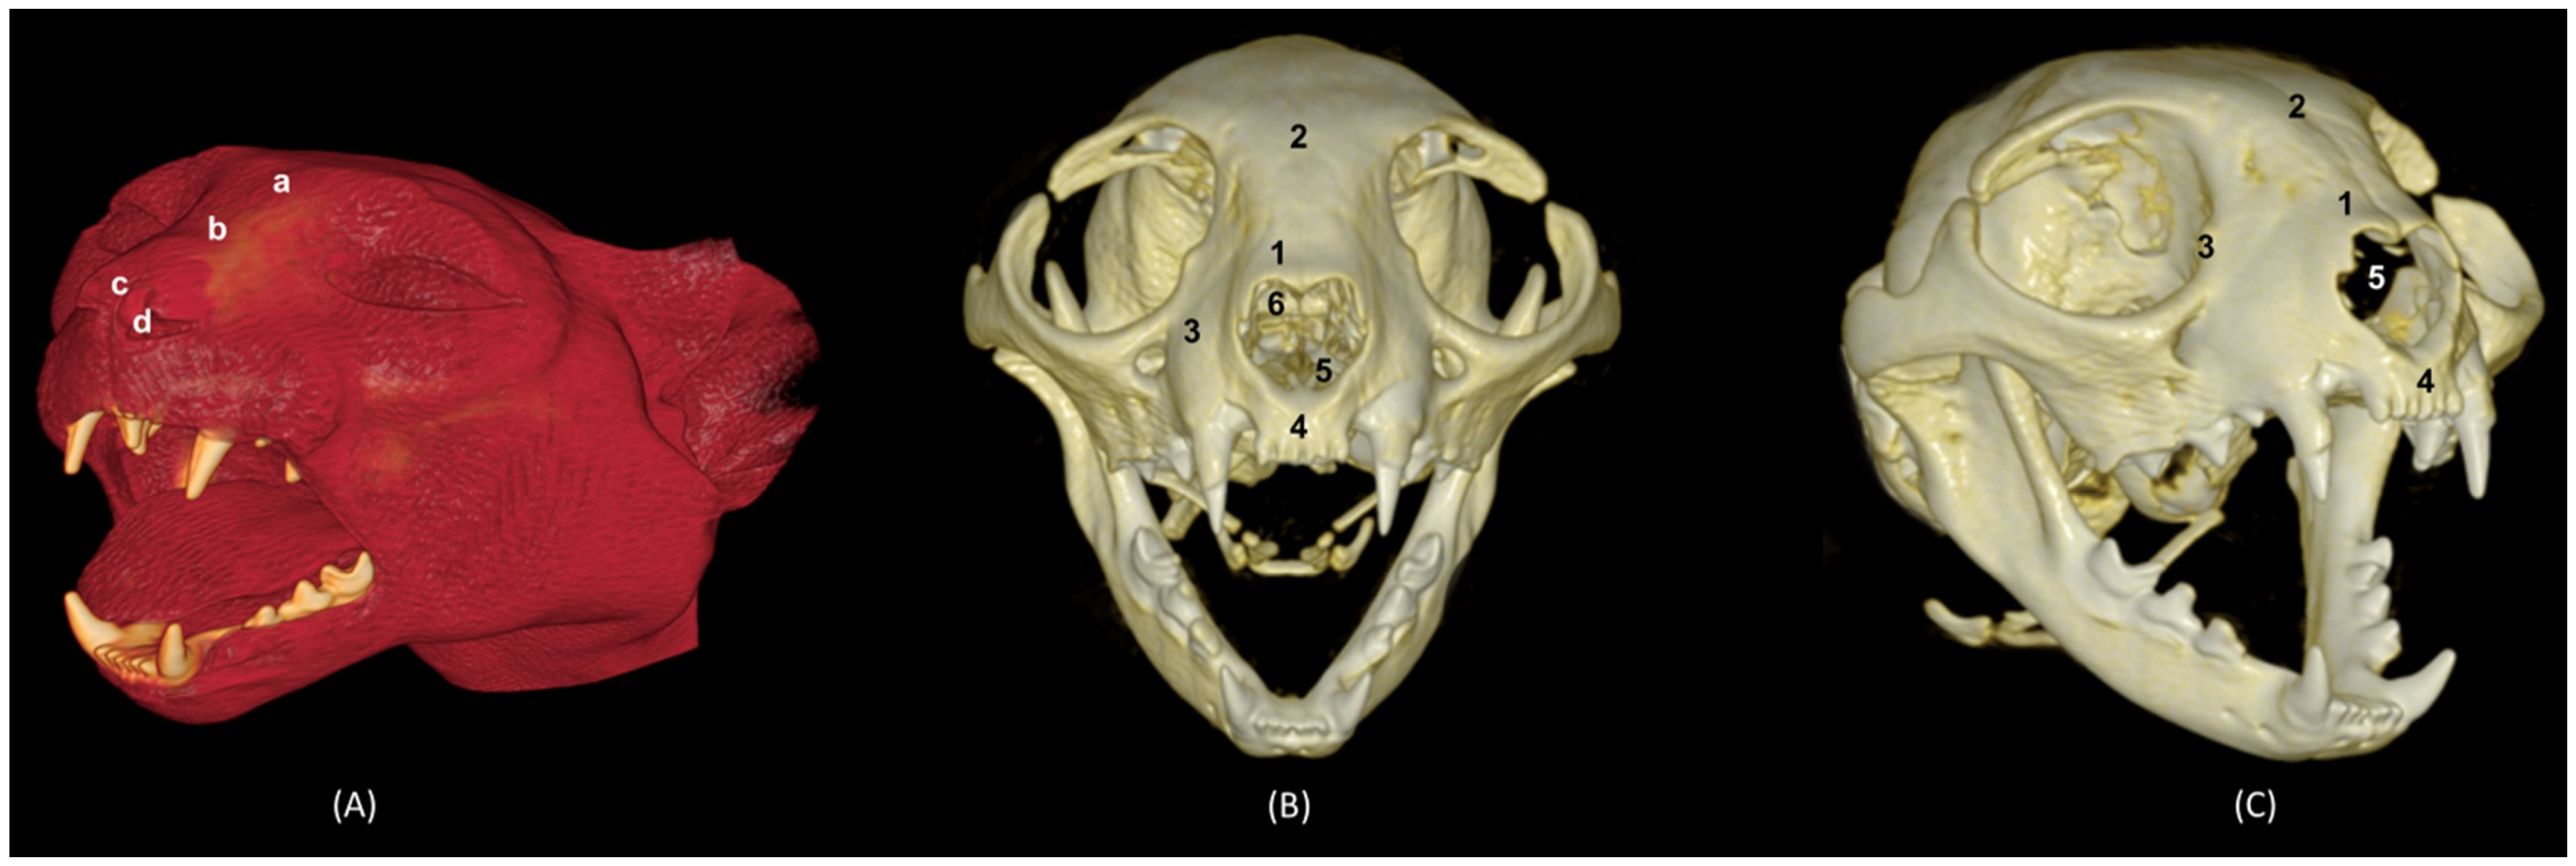

Figure 31 shows the reconstructed leopard images. The nasal plane and the bony framework that supports the nasal cavity were clearly observed, as well as the boundaries between these bones. In this way, we visualized the frontal and the nasal bones, laterally the maxilla and ventrally the most rostral side of the incisive bone.

Figure 31. OsiriX 3D reconstructed CT images of the leopard’s head showing the external nares and nasal plane. (A): VR surface reconstruction. Rostral view. (B): VR deep reconstruction. Rostral view. (C) VR deep reconstruction. Right rostrolateral view. a. Root of the nose; b. Dorsum of the nose; c. Tip of the nose; d. Nasal orifice; 1. Nasal bone; 2. Frontal bone; 3. Maxilla; 4. Incisive bone; 5. Nasal cavity; 6. Turbinates.

In the lion CT VR images (Figure 32), we could also observe the external nose and these bones. However, the morphology of these skulls differed from the rest. The short rostral extension of the nasal bone was observed, as well as the convex morphology that the frontal bone acquires. The bone structure was much more compact than in other felines.

Figure 32. OsiriX 3D reconstructed CT images of the lion’s head showing the external nares and nasal plane. (A): VR surface reconstruction. Rostral view. (B): VR deep reconstruction. Rostral view. (C) VR deep reconstruction. Right rostrolateral view. a. Root of the nose; b. Dorsum of the nose; c. Tip of the nose; d. Nasal orifice; 1. Nasal bone; 2. Frontal bone; 3. Maxilla; 4. Incisive bone; 5. Nasal cavity; 6. Turbinates.

In the reconstruction of the cheetah’s head (Figure 33), the limit between the frontal and nasal bones was not so pronounced. The frontal bone in the cheetah was completely concave, unlike the lion.

Figure 33. OsiriX 3D reconstructed CT images of the cheetah’s head showing the external nares and nasal plane. (A): VR surface reconstruction. Rostral view. (B): VR deep reconstruction. Rostral view. (C) VR deep reconstruction. Right rostrolateral view. a. Root of the nose; b. Dorsum of the nose; c. Tip of the nose; d. Nasal orifice; 1. Nasal bone; 2. Frontal bone; 3. Maxilla; 4. Incisive bone; 5. Nasal cavity; 6. Turbinates.

Finally, the VR reconstruction of the domestic cat skull (Figure 34) showed that the bone limits were not as noticeable as in the leopard or cheetah. The frontal bone represents a large extension since its zygomatic process developed very laterally, unlike in big felids.

Figure 34. OsiriX 3D reconstructed CT images of the cat’s head showing the external nares and nasal plane. (A): VR surface reconstruction. Rostral view. (B): VR deep reconstruction. Rostral view. (C) VR deep reconstruction. Right rostrolateral view. a. Root of the nose; b. Dorsum of the nose; c. Tip of the nose; d. Nasal orifice; 1. Nasal bone; 2. Frontal bone; 3. Maxilla; 4. Incisive bone; 5. Nasal cavity; 6. Turbinates.